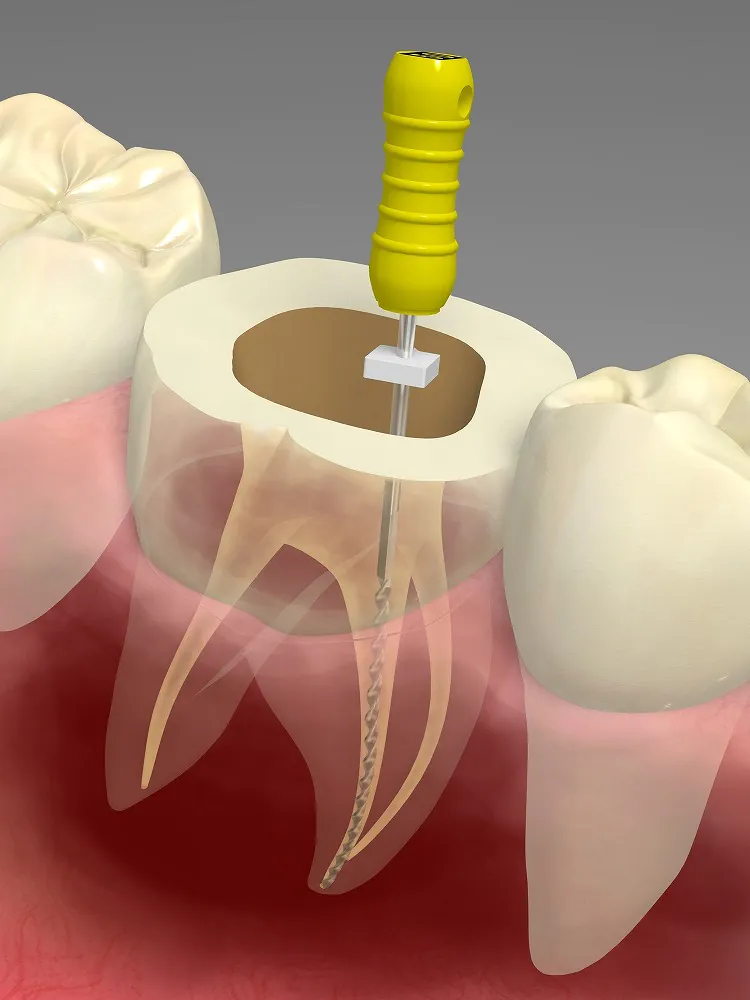

ニッケルチタンファイル

ニッケルチタンは、根管内の神経や血管などを取り除く際に使用する「ファイル」の一種です。保険診療ではステンレス製のファイルが使用されますが、これはニッケルチタンファイルと比較すると、柔軟性に欠けるため、複雑に入り組んだ根管内のすみずみまでアプローチすることが困難です。ニッケルチタンファイルは、ステンレスファイルに比べて柔軟性があります。そのため、根管を傷つけずに、感染組織をしっかりと取り除くことが可能です。当院では、保険診療内でも精度の高い治療を心がけていますが、根管治療の成功率を高めるためにニッケルチタンファイルをおすすめします。

根管治療は、根管内の感染組織を取り除き、薬を詰めて密閉し、歯の形態を被せ物で補うことで歯の機能を取り戻す治療法です。むし歯が進行すると、歯の内部にある根管を通る神経が感染し、痛みを引き起こすことがあります。根管治療では、この神経をリーマーやファイルによって取り除きます。そして、根管内に残っている可能性がある細菌を殺菌するために、消毒薬を根管内に充填します。消毒した後、根管内に適切な詰め物を詰めて、根管内に再び細菌が入らないようにします。最後に、歯の形態を被せ物で補えば根管治療は終了です。

根管治療は、根管内の感染組織を取り除き、薬を詰めて密閉し、歯の形態を被せ物で補うことで歯の機能を取り戻す治療法です。むし歯が進行すると、歯の内部にある根管を通る神経が感染し、痛みを引き起こすことがあります。根管治療では、この神経をリーマーやファイルによって取り除きます。そして、根管内に残っている可能性がある細菌を殺菌するために、消毒薬を根管内に充填します。消毒した後、根管内に適切な詰め物を詰めて、根管内に再び細菌が入らないようにします。最後に、歯の形態を被せ物で補えば根管治療は終了です。